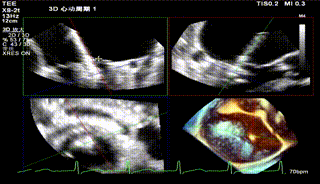

第二枚夹子释放后血流3D

怎么上穿刺鞘攻克巨大左房伴转位穿刺难关!温医大附一院周浩教授团队创新应用“导丝定位+可调弯鞘”技术完成高难度TEER手术_https://www.jmylbn.com_新闻资讯_第37张

第2枚夹子释放后压差

送入第二枚SW0609(短宽型)二尖瓣夹,使其紧贴第一枚夹子。在食道心脏超声三维多平面重建(3D-MPR)引导下,将夹子跨瓣送入左心室。首次尝试捕捞并夹持瓣叶后关闭夹子,外侧反流量仍较多;随后反转夹子并重新捕捞夹持成功,此时前后叶活动均受限,外侧反流显著减少。释放夹子后,三维超声显示组织桥稳定,反流减轻至轻中度,平均跨瓣压差未见狭窄征象,肺静脉逆流亦有所改善。

术后残留瓣口面积3.95cm²